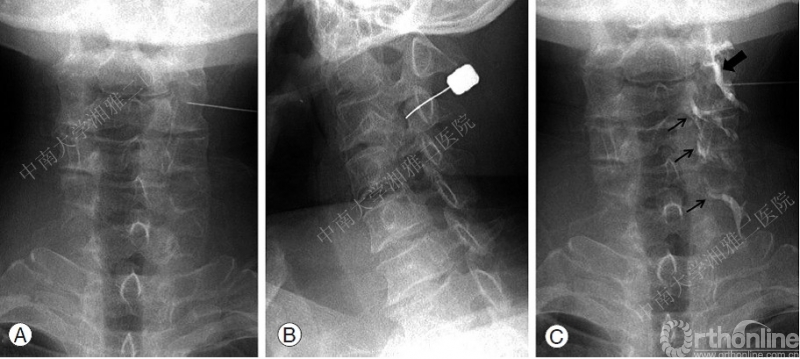

SCNRB技术操作步骤(图1):

1. 透视下准确定位穿刺节段及侧别(C臂引导下通常需要将颈动脉血管鞘向旁边推移,超声引导下穿刺则经过前中斜角肌间隙);

2. 45度倾斜角投照使椎间孔形态最大化,目标节段椎体上终板前后重叠;

3. 利用共轴技术穿刺,以椎间孔背侧即紧贴上关节突腹侧进针;

4. 前后位投照保证针尖始终不超过关节柱中线;

5. 回抽无血及脑脊液,先后分别注射0.5ml造影剂和局麻药,显影及阻滞目标神经根。

图1:SCNRB穿刺路径

5. 小剂量非离子型造影剂注射进行目标神经根显影(1ml的造影剂经C3/4椎间孔注射可以向下扩散相邻的三个节段水平)(图2)

图2: A. 造影前前后位

B. 造影前斜位

C. 造影后前后位